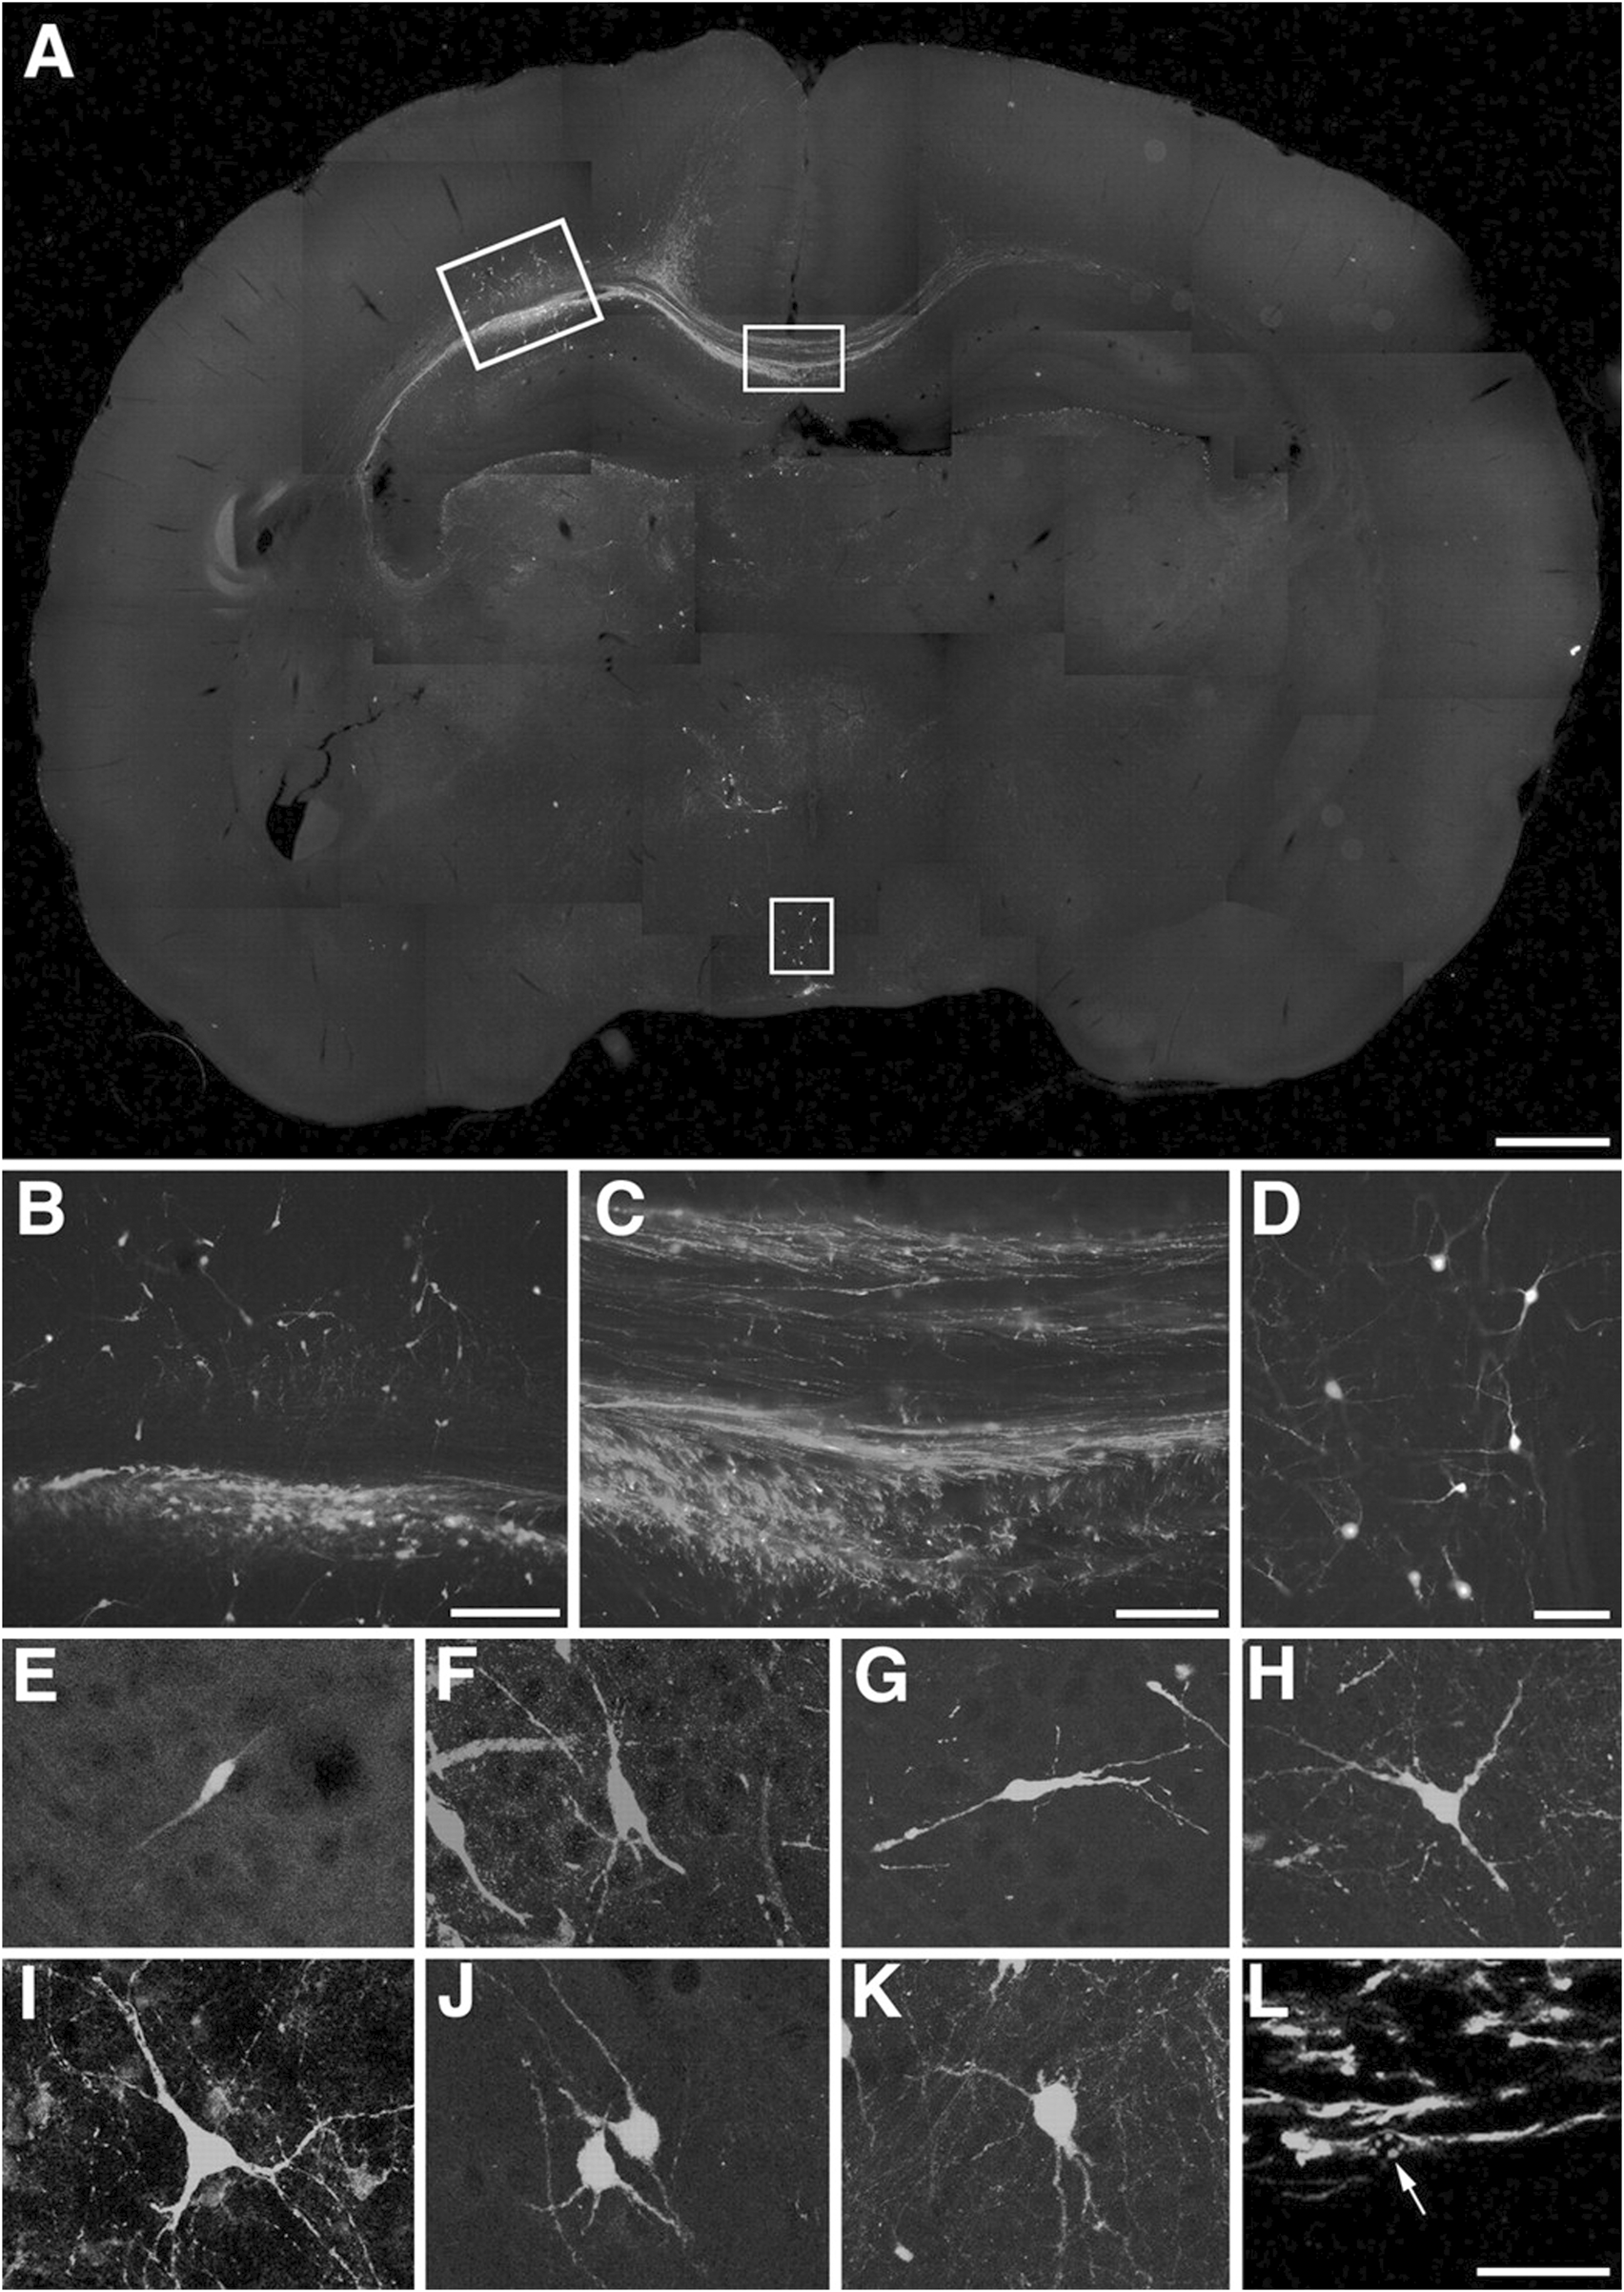

In mouse models of AD, transplantation of these differentiated neurons has shown that they can survive, migrate within the host brain, and form synaptic connections with endogenous neurons (Hayashi et al., 2020; Yang et al., 2016b; Hermann and Storch, 2013). It has confirmed the expression of cholinergic markers such as choline acetyltransferase (ChAT) and synaptophysin, as well as the ability to release acetylcholine (Gu et al., 2015). Moreover, as shown in Figure 3, EGFP fluorescence demonstrates that the transplanted neurons are capable of generating action potentials, suggesting functional integration into neural circuits (Wernig et al., 2004a). Some studies have also reported behavioral improvements in learning and memory tasks in treated animal models, indicating preliminary functional recovery (Kim et al., 2015; Wang et al., 2015).

FIGURE 3

Incorporation of ES cell-derived neurons into the developing rat brain. (A–K) Engrafted donor cells identified by their EGFP fluorescence (E,G–K) or immunofluorescence with an antibody to EGFP (A–D,F) generate a variety of neuronal phenotypes. A, Twenty days after transplantation into the ventricle of E16.5 rats, the cells formed intraventricular clusters and migrated as single cells into various host brain regions. (B–D) Higher power microphotographs of areas indicated in (A) depicting incorporation into neocortex(B)and hypothalamus(D). Donor-derived cortical neurons were found to extend long axons into the corpus callosum (C). (E–K) Confocal microscopy and digital reconstruction revealed that the transplanted cells adopt a variety of morphologies, including simple bipolar cells resembling young migratory neurons (E, neocortex), complex phenotypes mimicking principal pyramidal neurons of the hippocampus (F, CA1pyramidalcelllayer), and multipolar cell types (G,H) neocortex; (I) septum; (J), thalamus; (K), tectum). (L) Immunofluorescence analysis with an antibody to nestin depicts engrafted cells with immature, elongated phenotypes characteristic of migratory precursor cells. The arrow points to the mouse-specific DNA in situ hybridization signal used for donor cell identification (tectum, confocal analysis). Scale bars: (A) 1 mm; (B) 200 m; (C) (D) 100 m; (E–L) 50 m (Wernig et al., 2004b).